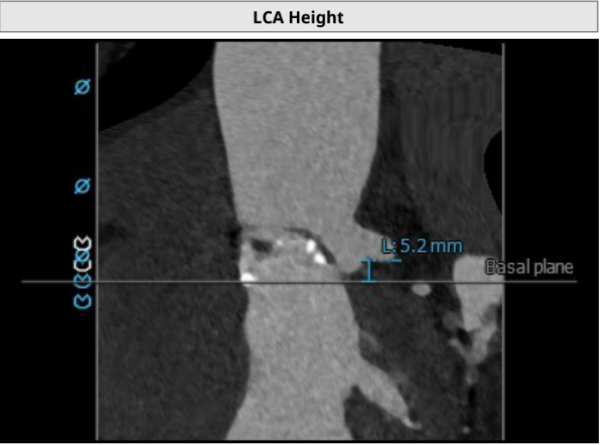

左冠开口高度5.2mm;右冠开口高度14.3mm。左冠开口低,瓣叶稍长,术中需球扩确认冠脉风险。

3.患者左侧冠脉开口高度低LCA:5.2mm,左冠瓣瓣叶长度约16.7mm;右侧冠脉开口高度可RCA:14.3mm。